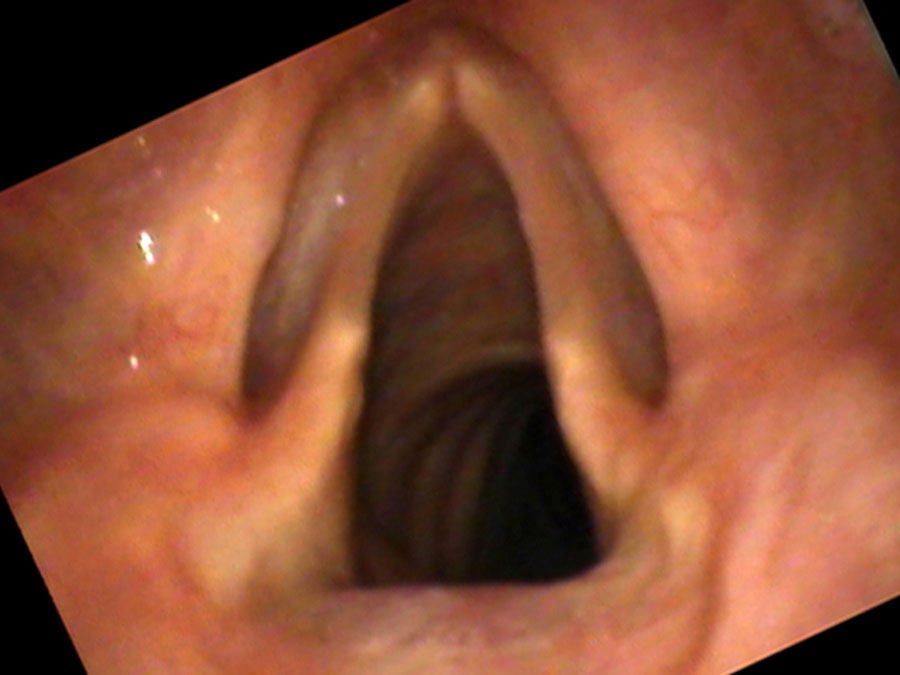

What surprises Joe’s daughter at the examination: when asked to yell, his voice sounds completely normal. “Dad, that is how your voice used to sound!” she exclaims. The yell works because explosive air pressure forces the cords together momentarily, overcoming the gap. Vocal underdoers often have not tried yelling — they are naturally not very talkative, so it simply hasn’t come up. But the preserved yell confirms the problem is not paralysis or scarring: the cords can close, they just lack the bulk to do so effortlessly at conversational volumes.

Joe’s decades of quiet railroad work followed by retirement created a long arc of vocal disuse. His cords thinned slowly and he adapted unconsciously — until socializing became so effortful and unreliable that he withdrew further still. When he yells, his voice sounds as it once did. That single observation — the preserved yell — is both diagnostic and therapeutic: it demonstrates to the patient and his family that the cords still have the potential to function well under the right conditions.